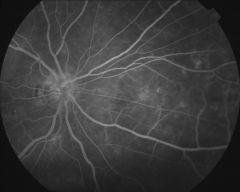

IM000020 |